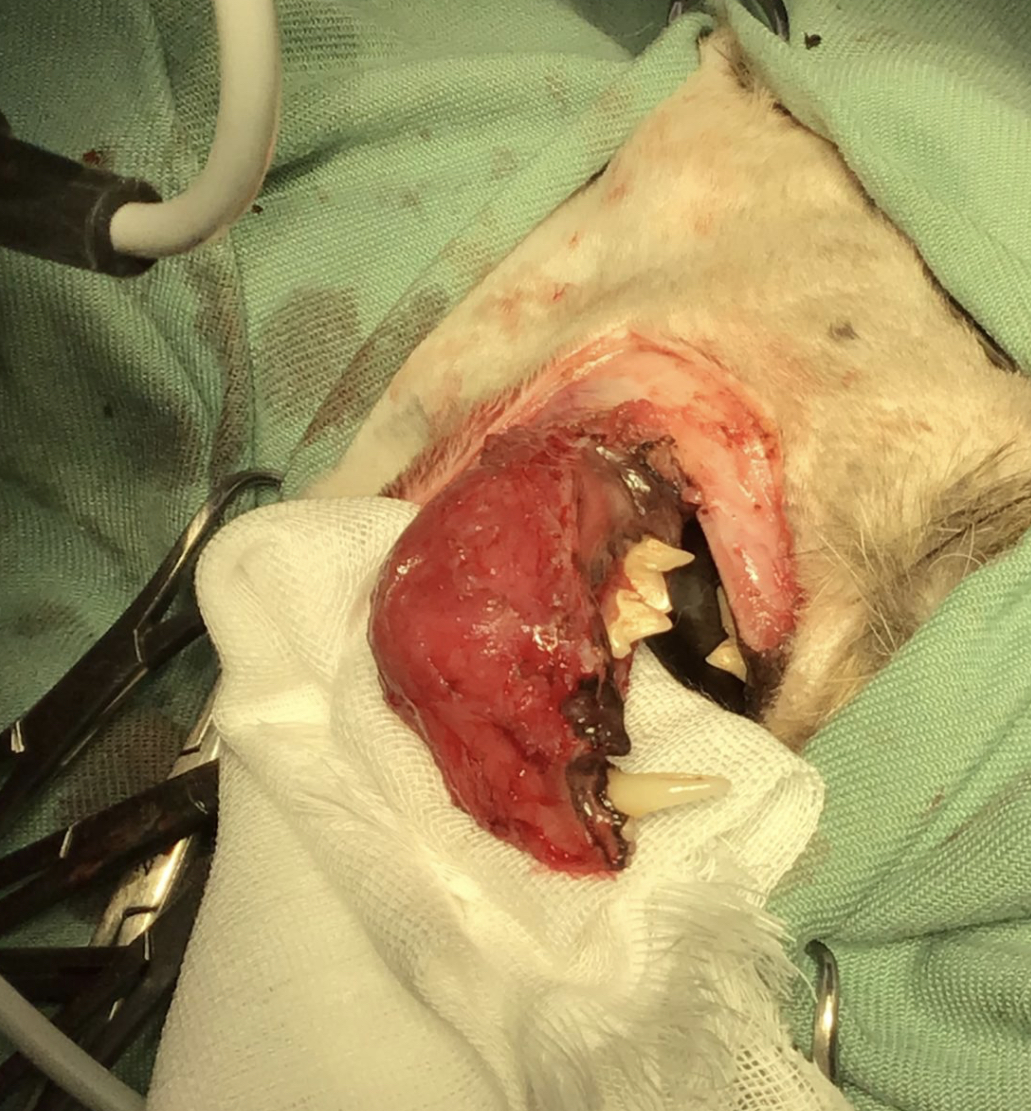

今回は、口腔内の悪性腫瘍である「扁平上皮癌」を患った中高齢の猫ちゃんの外科症例についてご報告します。他院にて右下顎の腫瘤から扁平上皮癌と診断され、セカンドオピニオンとして当院へ転院されてきた患者さんです。口腔内悪性腫瘍は進行が早く、生活の質を著しく損なう疾患です。本記事では、顎骨を切除するという根治的あるいは緩和的な大手術の現実と、術後に待ち受ける合併症のリスク、そしてご家族に求められる在宅ケアの現実について客観的な事実に基づき解説します。

扁平上皮癌は局所浸潤性が極めて高く、単なる腫瘤の切除では直ちに再発します。骨浸潤が認められるため、外科的適応としては腫瘍を骨ごと切除する「下顎の切除」が必須と判断しました。

本症例に対しては、以下の外科処置および内科的治療を統合して実施しました。

This case report details the surgical management and post-operative care of a middle-aged/senior cat diagnosed with oral squamous cell carcinoma (SCC). Due to bone invasion, a partial mandibulectomy (limited to up to 3/4 of the mandible) and commissurorrhaphy were performed, alongside the placement of an esophagostomy tube. Post-operative care included targeted therapy (Toceranib/Palladia) and rigorous home management by the family. Despite severe complications, including an ESBL-producing E. coli infection managed topically, and a local tumor recurrence at six months post-surgery, the patient has achieved a long-term survival of over four years. This highlights the realities, clinical limitations, and potential of aggressive surgical and medical intervention combined with dedicated owner care.